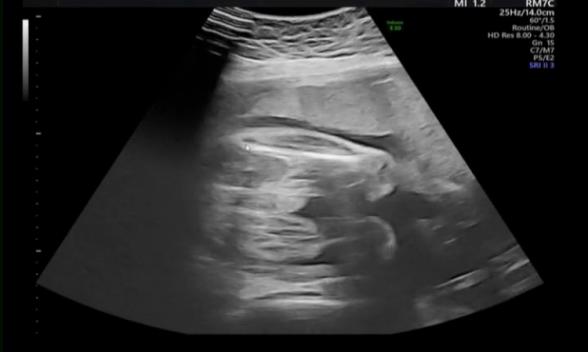

またもやご質問申し訳ないのですが、先生はこのエコー写真を見て、男児の外性器がしっかりついていると思われますでしょうか?。>_<。

赤ちゃんのエコー写真についてですね。

ついているようにも見えますが、断定はできません。